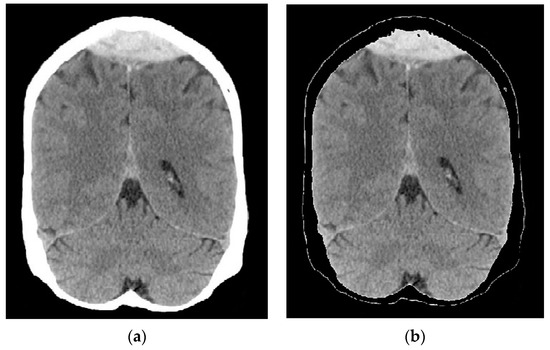

2.2. Image Preprocessing and Segmentation

2.2.1. Image Segmentation